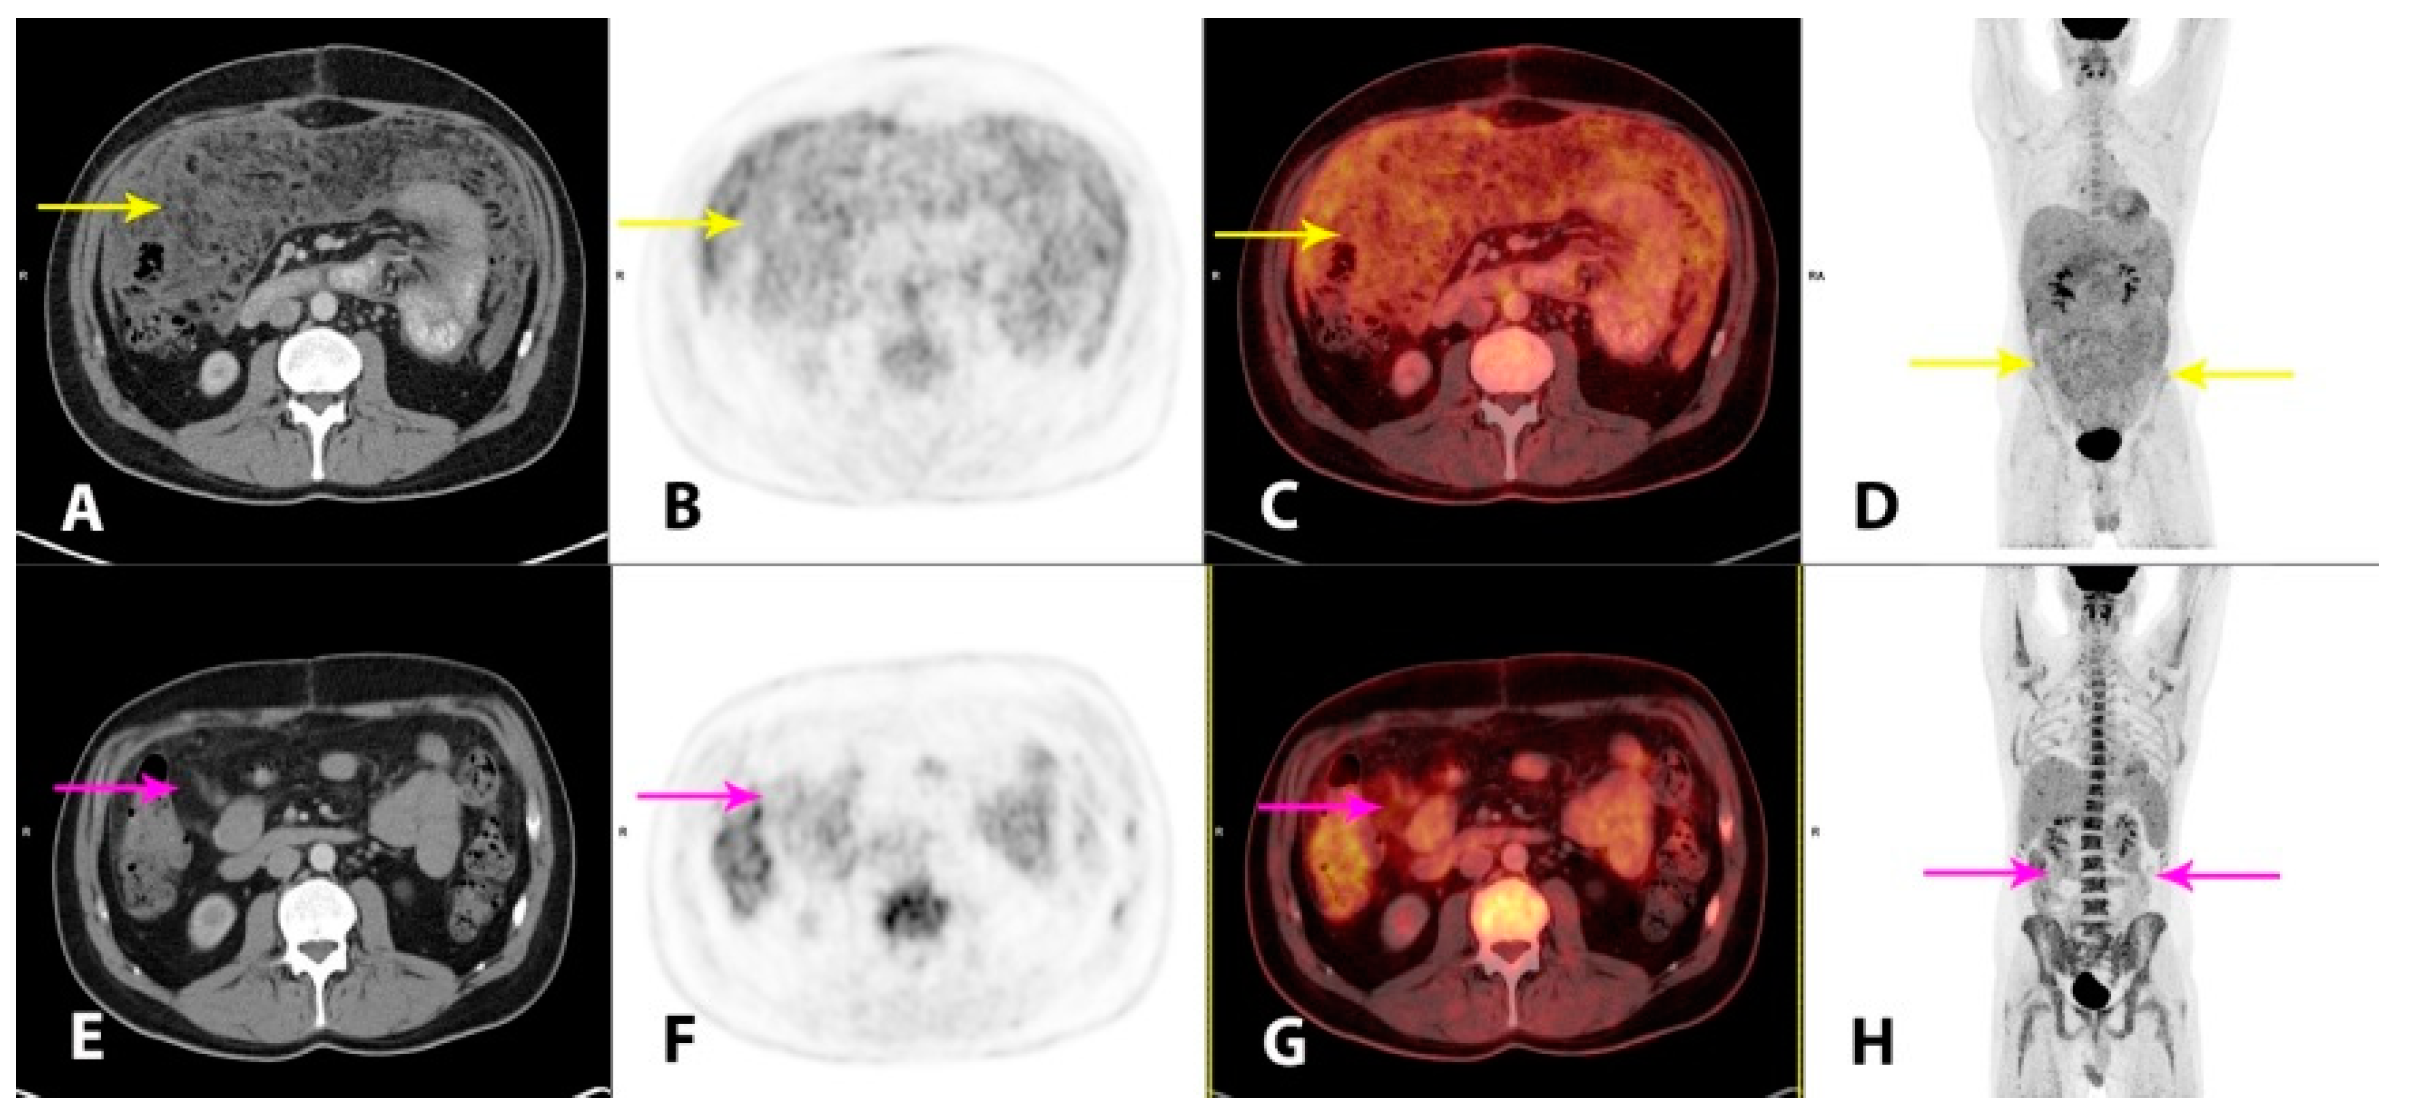

Hybrid imaging with 2-deoxy-2-[18F]fluoro-D-glucose positron emission tomography/CT (2-[18F]FDG PET/CT) was performed for the staging of the disease and as baseline for monitoring of the treatment response. Imaging performed 1 h post-injection of 4.0 MBq/kg 2-[18F]FDG showed a moderately metabolically active, irregular thickening of the peritoneal folds and extensive carcinomatosis-like infiltration in the omentum, mesentery and the pelvic cavity (A–D, yellow arrows). There was minor ascitic fluid in the abdominal and pelvic cavities. There were also metabolically active, enlarged lymph nodes in the mediastinum and upper retroperitoneum. The findings were considered highly suspicious for malignancy. At this point, plasma lactate dehydrogenase (LDH) levels, a future tumor marker in this patient, were elevated (366 U/L; reference range 105–205 U/L). An initial steroid treatment with prednisolone 100 mg/daily had a good effect on the tendency of the recollection of ascites. However, as no standardized treatment for this patient category without comorbidity exists, a hematological specialized tumor board, after consent from the patient, decided to administer a chemotherapy regimen of ifosfamide, carboplatin and etoposide (ICE), which was initiated one month after initial hospitalization. The patient tolerated the treatment well. At clinical follow-up after two cycles of ICE, the patient’s wellbeing was improved, the plasma LDH was normalized and imaging with 2-[18F]FDG PET/CT demonstrated a substantial partial response (PR), both metabolically and morphologically, of the previously described findings in the peritoneum. There were still metabolically active, carcinomatosis-like findings in the omentum, mesentery and on the liver surface (E–H, magenta arrows). There were no pathological lymph nodes. After completion of four cycles of ICE, the metabolic complete response (CR) and a further morphological PR were reported on follow-up 2-[18F]FDG PET/CT (not shown). The plasma LDH was still within a normal range. The patient tolerated the fifth and final cycle of ICE well.